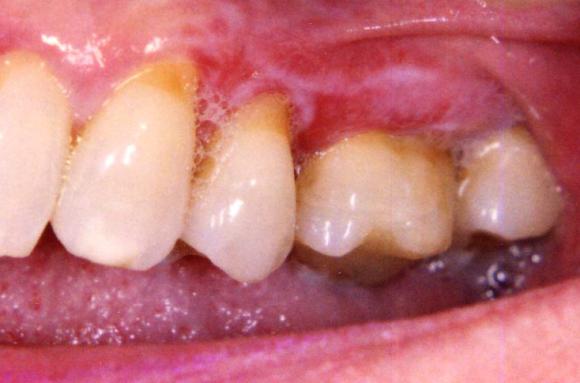

Lichen planus näkyy yleensä valkoisina, verkkomaisina juovina tai laikkuina symmetrisesti poskien limakalvoilla, kielessä tai ikenillä.

Lichen voi myös aiheuttaa kipua, polttelua ja/tai arkuutta suun limakalvoilla. Muutokset voivat ilmetä valkoisina tai punaisina alueina, haavaumina tai rakkuloina. Ikenet voivat ohentua ja tulla punaisiksi ja kiiltäviksi. Hampaiden harjaus voi hankaloitua.

Lichen planus ikenissä